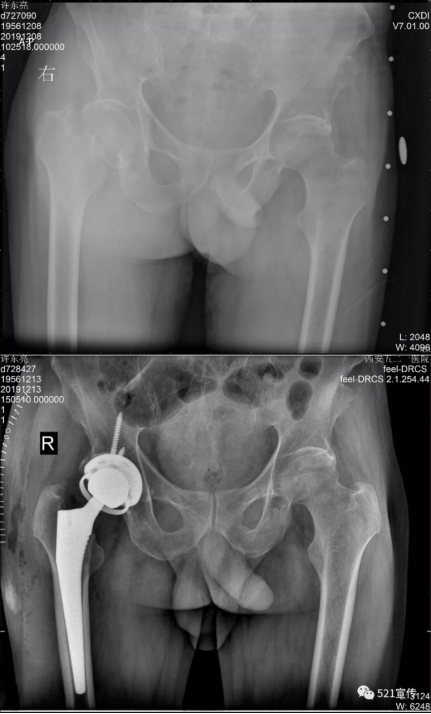

兵器工业521医院完成首例限制性内衬的全髋关节置换手术

近日,兵器工业521医院成功完成首例限制性内衬的全髋关节置换手术。目前患者恢复良好。63岁的患者许先生因右侧股骨颈骨折,来到521医院关节外科就诊。患者患脊髓型颈椎病,右侧肢体踩棉花感,肌力弱,无内科基础疾病。若不及时治疗,将严重影响患者生活质量。而且患者相对年轻,活动量大,但右下肢肌力弱,普通的全髋关节置换术后脱位的风险较高。在充分征求患者及家属意见后,经副院长张朝、关节外科主任吴勐及其团队反复仔细讨论,制定手术计划,决定为患者选用限制性内衬的全髋关节置换假体。此假体能满足患者日常生活需求,并可降低术后脱位风险。术后次日,患者即可下地行走。该假体对于相对年轻但下肢肌力较弱的患者,既可满足患者日常生活,又可降低术后脱位的风险,具有极大的医学前景及临床意义。